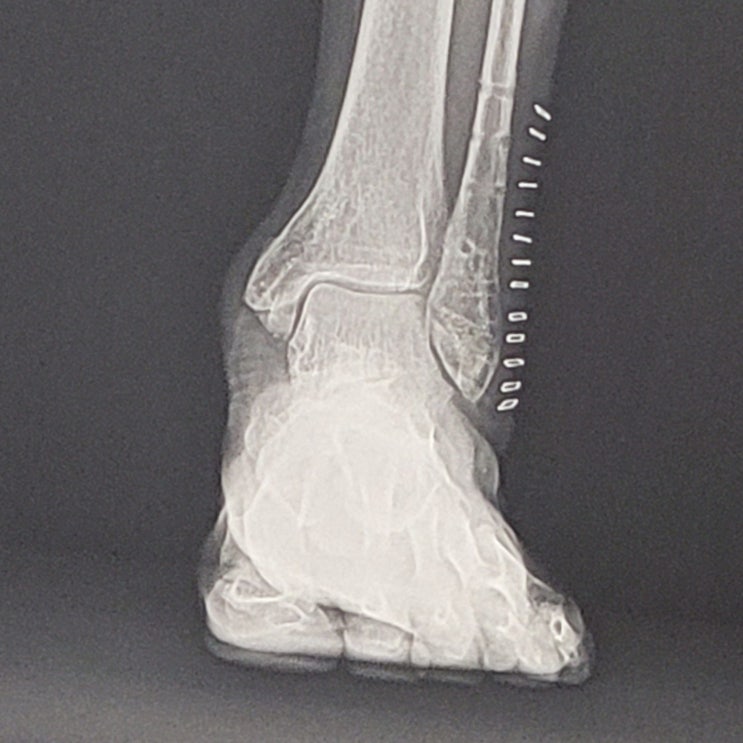

발목 골절 수술 후기, 드디어 몸에 있는 철 모두 제거하다, 모닝 산책의 즐거움

드디어 몸에 있는 철(1차 수술 핀 삽입, 2차 수술에서 핀 제거, 꿰매면서 발목 바깥쪽 스테이플러스 13개, ...